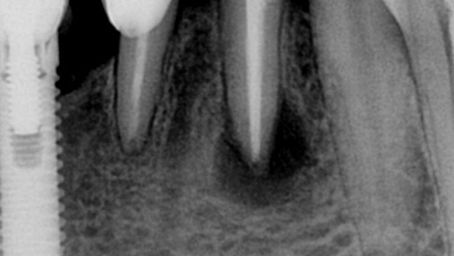

Casos clínicos

Explore nossos casos clínicos sobre o uso de cimento biocerâmico Cimmo: aplicações reais, abordagens práticas e resultados transformadores para inspirar e aprimorar sua prática odontológica.